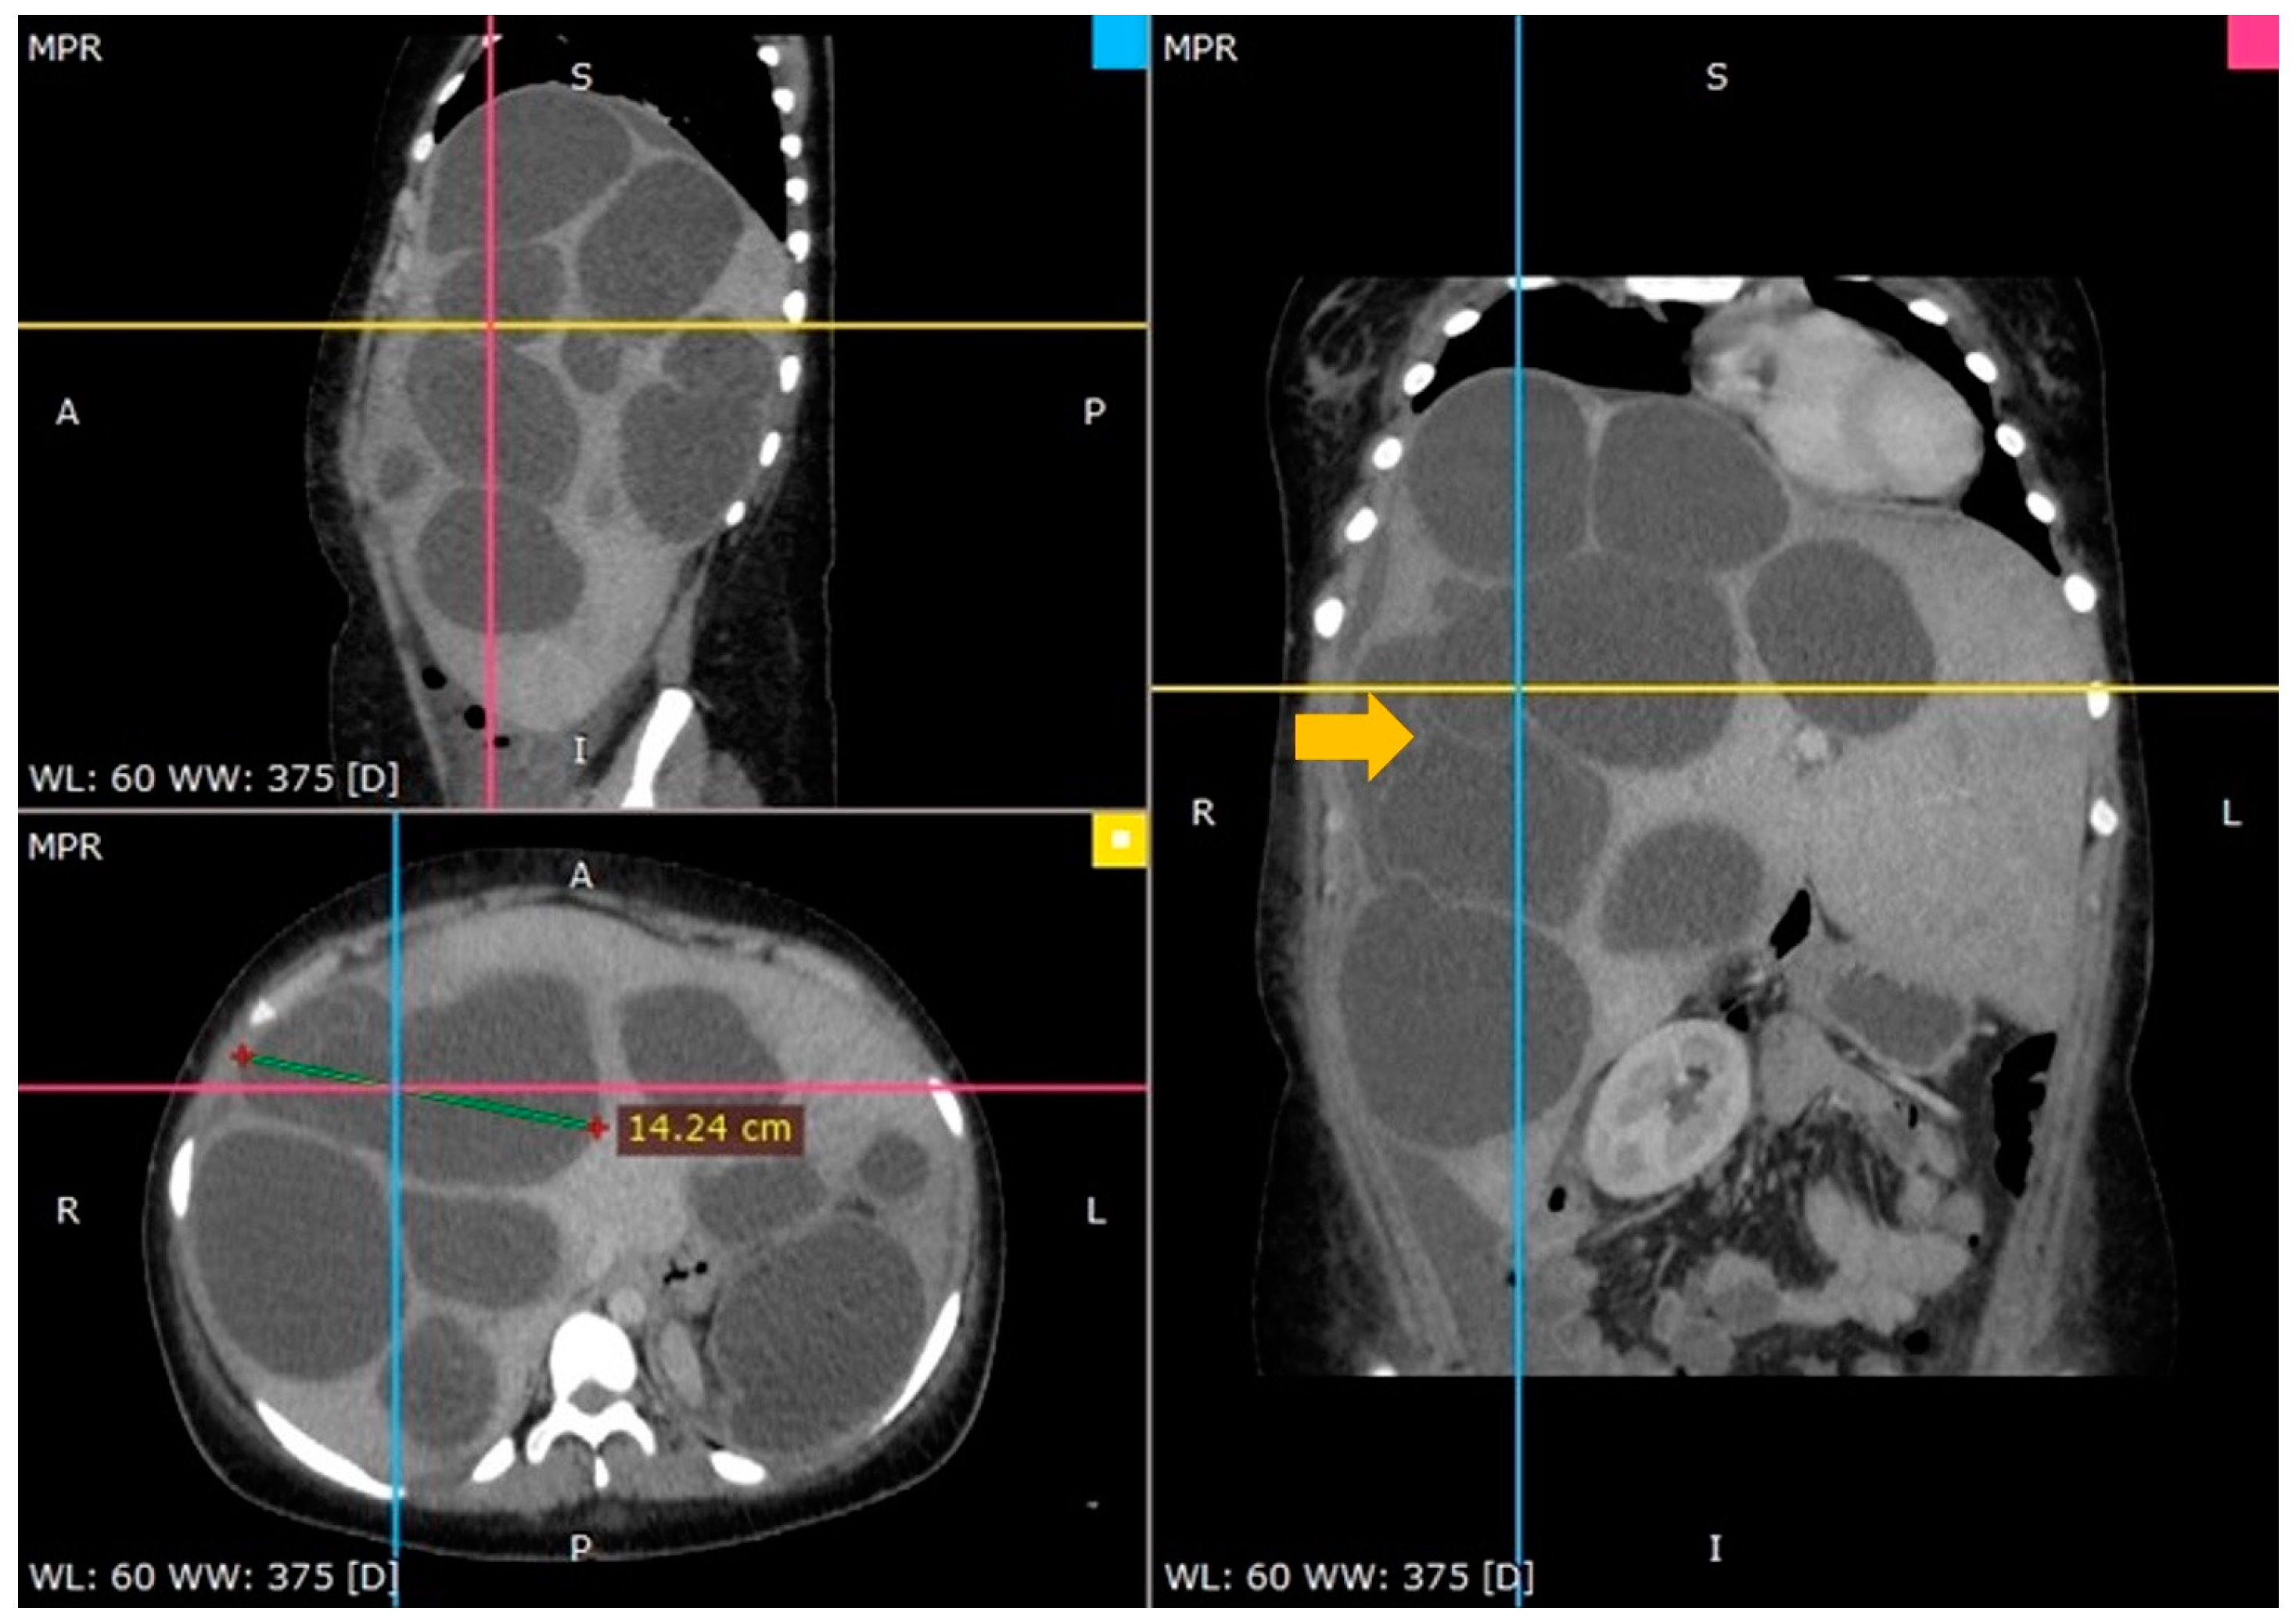

3.2. Case 2